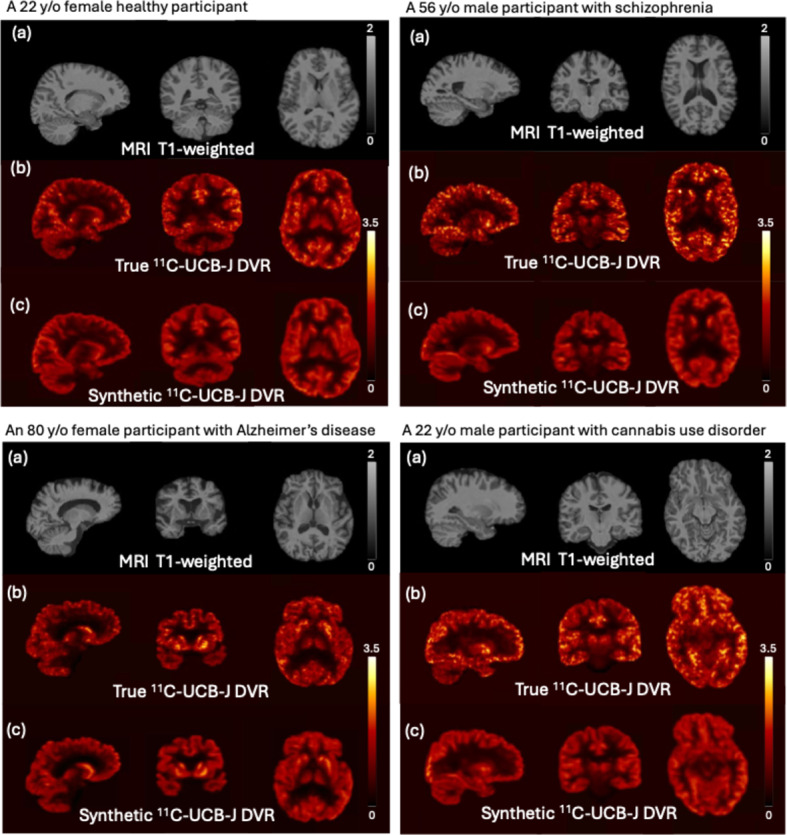

Methods: We implemented a convolution-based 3D encoder-decoder to predict [11C]UCB-J SV2A PET images. A total of 160 participants who underwent both MRI and [11C]UCB-J PET imaging, including individuals with schizophrenia, cannabis use disorder, Alzheimer's disease, were used in this study. The model was trained on pairs of T1-weighted MRI and [11C]UCB-J distribution volume ratio images, and tested through a 10-fold cross-validation process. The image translation accuracy was evaluated based on the mean squared error, structural similarity index, percentage bias and Pearson's correlation coefficient between the ground truth and the predicted images. Additionally, we assessed the prediction accuracy of selected regions of interest (ROIs) crucial for brain disorders to evaluate our results.

Results: The generated SV2A PET images are visually similar to the ground truth in terms of contrast and tracer distribution, quantitatively with low bias (< 2%) and high similarity (> 0.9). Across all diagnostic categories and ROIs, including the hippocampus, frontal, occipital, parietal, and temporal regions, the synthetic SV2A PET images exhibit an average bias of less than 5% compared to the ground truth. The model also demonstrates a capacity for noise reduction, producing images of higher quality compared to the low-dose scans.